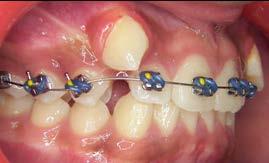

Tratamiento de caninos retenidos superiores en paciente en crecimiento con clase II división 2. Reporte de caso clínico

Los caninos retenidos constituyen una alteración eruptiva frecuente, con mayor prevalencia en la arcada superior. Su etiología es multifactorial y puede interferir con el trayecto normal de erupción, comprometiendo la oclusión y la estética.

Objetivo: Corregir una maloclusión Clase II división 2 mediante tratamiento ortodóntico en un paciente en crecimiento con ambos caninos superiores retenidos. Metodología: Se presenta el caso de un paciente masculino de 12 años, en dentición permanente, con perfil convexo, patrón dolicofacial y Clase II esquelética. Se realizó tratamiento ortodóntico sin extracciones. Para la tracción y alineación de los caninos retenidos se emplearon resortes abiertos (open coil springs) para la creación de espacio. Resultados: